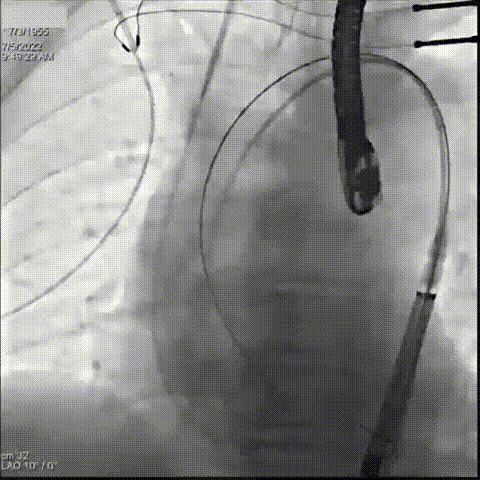

术前CT评估患者Annulus 75mm,STJ 89.3mm,左室流出道面积25.1mm²,周长77.3mm。综合各项评估,手术团队计划在全麻状态下,经患者右侧股动脉入路植入一枚23mm Evolut PRO瓣膜行主动脉瓣置换手术。

手术最终取得成功,患者术后状态良好。